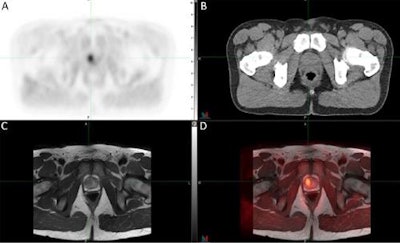

The researchers performed C-11 sarcosine PET studies in two mice with prostate cancer and one human with localized prostate cancer characterized as Gleason 4 + 3. PET studies with C-11 choline also were performed for comparison.

The researchers found that in the mouse models, the C-11 sarcosine studies showed elevated levels of tumor-to-background ratio compared with the C-11 choline studies. In the human case, C-11 sarcosine PET produced high-contrast images. Additional analysis of target metabolites found that levels of sarcosine, glycine, and choline were higher in localized prostate cancer compared with benign tissue.